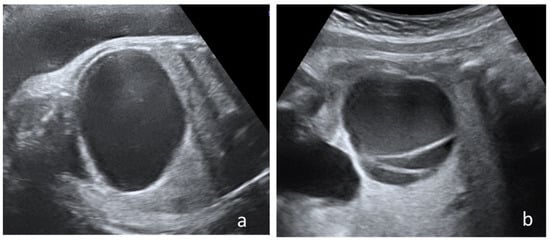

Some of the prenatal IRM aspects (simple cyst, complex cysts, hemorrhagic cyst, and ovarian torsion) are depicted in Figure 4.

MRI correctly identified ovarian torsion in all cases and had an important contribution to the diagnosis of intracystic hemorrhagic changes and helped in establishing differential diagnoses.

Figure 4. Fetal ovarian cyst-MRI aspects. All images are T2 SSFSE (single shot fast spin echo): (a) Simple ovarian cyst. Coronal view with a fluid filled cyst (arrow); (b) hemorrhagic cyst. Sagittal view with an inhomogeneous cyst, with hypointense fluid-fluid level (arrow); (c) hemorrhagic cyst. Sagittal view showing a cyst with hemorrhagic hypointense content and fluid-fluid level (arow); (d) daughter cyst. Coronal view showing a hemorrhagic daughter cyst in a larger fluid filled cyst (arrow); (e) septated ovarian cyst. Axial view showing a cyst with fine internal septations and uncomplicated fluid hyperintensity (arrow); (f) ovarian torsion. Enlarged ovary with inhomogeneous structure and a fluid-filled cyst, mimicking a fluid-fluid level (arrow).